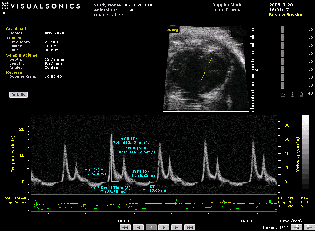

超声成像是一种实时、动态、直观、无辐射、非侵入式的活体成像,被广泛应用于医疗领域。高分辨率小动物超声机的问世,使得在组织、器官水平上对实验动物疾病发生发展的过程进行动态监测成为可能,小动物超声成像也逐渐成为生物医学研究的重要手段,在心血管研究、肿瘤学、发育生物学、再生医学、药物研发等领域发挥着巨大作用。早在2006年,本实验室从加拿大引入国内首台小动物超声机Vevo 770,之后又引入新机型Vevo 2100,小动物超声平台一直在技术上处于国内领先水平并与国际水平保持同步,在心血管结构和功能的评价方面工作尤为突出,为科研工作提供了不可或缺的重要支撑。现有Vevo2100小动物超声成像系统具有多种图像采集模式:B-mode, M-mode, Color Doppler mode, PW doppler mode, 和PW tissue doppler mode等。可以实现对心血管结构和功能的检测,如室壁厚度、左室收缩功能、左室舒张功能、血流动力学、心壁运动异常、血管成像、动脉斑块及动脉瘤的形成等;对肿瘤的形成和血液供应进行评价;对腹部脏器的检测等等。小动物超声平台已连续多年不断支持高质量文章发表在Circulation, European Heart Journal, Circulation research, Nature Communications, Cell research等国际一流学术期刊上。